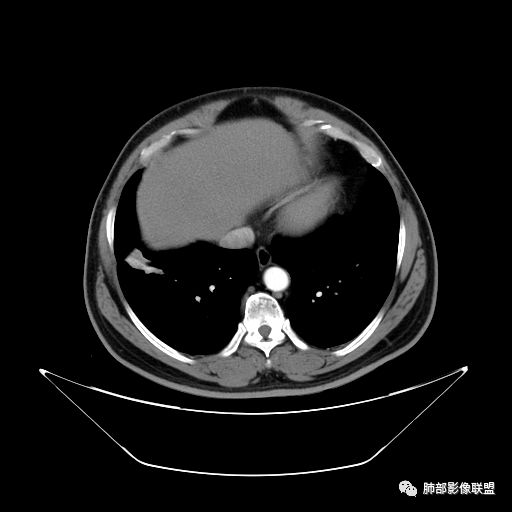

平安是福:平扫31Hu,动脉期33–42Hu,静脉期,39–54Hu。

1.左上胸内脊柱旁半圆形肿块,质地坚实,密度比较均匀。

2.病灶周边见胸膜掀起,应当考虑胸壁或是纵隔来源,肺内病变不会如此。

3.降主动脉这一相对固定结构向前方推移,提示病灶相对坚实且有牢固附着点,不支持来自柔软的肺组织。

就如同在腹部,能将肾脏推移的包块,应该来自腹膜后。

4.可疑肋间动脉病供血,提示肿块来自后纵隔的可能性。

5.相邻椎间孔未见扩大,也未见块影延入椎管,易起自于神经根的鞘瘤似乎找不到相关支持点。

6.未提供矢状位骨窗图像,如在肋骨内下缘观察到压迹有助于肋间神经的鞘瘤的判断,这是因为二者之间密切的毗邻关系。

7.静脉期轻度强化,注意不是环形强化,亦未显示明确的“AB区”,神经鞘瘤与副节瘤亦未找到支持点。

综上,病灶定位胸壁或后纵隔,就发病率而言,神经源性可能性较大。